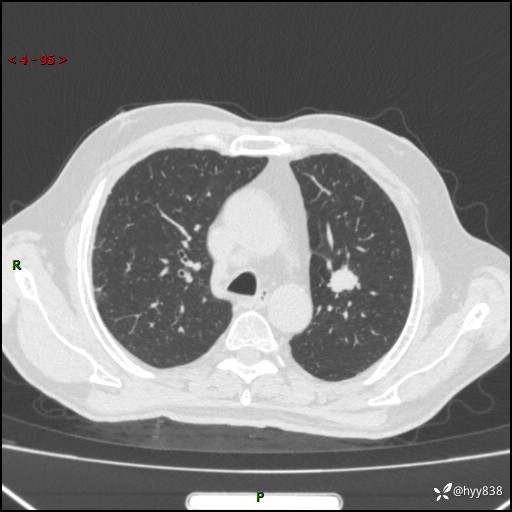

简要病史:患者4月前无明显诱因后背正中间疼痛,间断阵痛,无低热、咳嗽,盗汗、咯血、胸痛、喘气等不适,2024-2-25当地第二人民医院胸部CT提示“1.双肺感染病变;2.左肺上叶及右肺中叶结节灶;3.双肺肺气肿并肺大泡4.纵膈淋巴结肿大5.主动脉及冠脉硬化,今为求明显结节性质遂来我院门诊就诊,门诊以“肺占位”收治入院。 起病以来,患者精神饮食睡眠一般,大小便正常,体力体重无明细变化。

辅助检查:CT

临床诊断:肺占位

胸部CT平扫